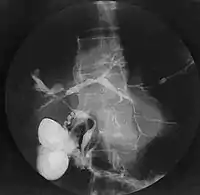

У гострій стадії опісторхозу в периферичній крові відзначають лейкоцитоз з еозинофілією (збільшення кількості еозинофілів, підвищення ШОЕ). Ці зміни максимально виражені на 2-3-му тижні захворювання. При біохімічному дослідженні виявляють підвищення активності АЛТ, АСТ, лужної фосфатази (ЛФ), гамма-глютамілтранспептидази (ГГТП), збільшений рівень загального білірубіну з переважанням прямої фракції. У хронічній стадії опісторхозу відзначають еозинофілію, іноді анемія з нормо- або макробластичним типом кровотворення. Функції печінки (білково-синтетична, пігментна, антитоксична) при неускладненому опісторхозі нормальні або незначно порушені. Виявляють підвищення активності амілази, ліпази в крові, діастази в сечі. При мікроскопії дуоденального вмісту спостерігають збільшення кількості лейкоцитів, епітеліальних клітин, а також детриту[28], кристалів білірубіну і холестерину (особливо в порції «С»). У половини хворих виявляють зниження кислотності шлункового соку. УЗД свідчить про підвищення ехогенності уздовж портальних трактів, наявність розширених жовчних проток, збільшення розмірів жовчного міхура, погане його скорочення навіть після призначення жовчогінних засобів або пробного сніданку, непрямі ознаки запалення в міхурі та жовчних протоках.